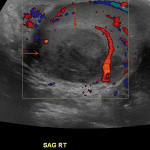

- Heterogeneous bilateral testicular echotexture with increased bilateral testicular and epididymal vascularity

- Rounded hypoechoic structure in the right testis measuring 2.8 x 2.7 x 2.1 cm without internal vascularity

- Moderate right and small left hydroceles with minimal internal echogenic debris but no loculations

- Edematous appearance of the scrotum

Segmental testicular infarct

Heterogeneous bilateral testicular echotexture with increased bilateral testicular and epididymal vascularity, concerning for bilateral epididymo-orchitis.

Rounded hypoechoic structure in the right testis measuring 2.8 x 2.7 x 2.1 cm without internal vascularity, which may represent a developing abscess, hypovascular or centrally necrotic testicular neoplasm, granulomatous disease, or segmental testicular infarct. Recommend urology consultation and followup imaging with ultrasound or MRI following treatment for further assessment.

Moderate right and small left hydroceles with minimal internal echogenic debris but no loculations, likely reactive.

Edematous appearance of the scrotum.